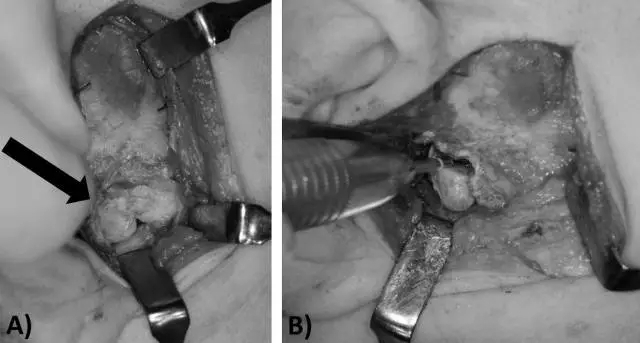

圖 3. 病例 2 的手術圖 (A) 耳前切口暴露關節(jié)窩及骨軟骨瘤(箭頭所示) (B)磨除骨軟骨瘤

手術方式及術中所見與病例 1 相似,切除骨腫瘤并修整關節(jié)窩,發(fā)現(xiàn)有慢性炎癥表現(xiàn)的關節(jié)盤,切除部分粘連后關閉傷口。